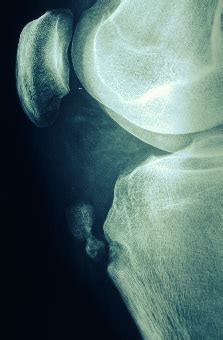

Рис. 245. Болезнь Осгуда-Шлаттера: а - варианты...